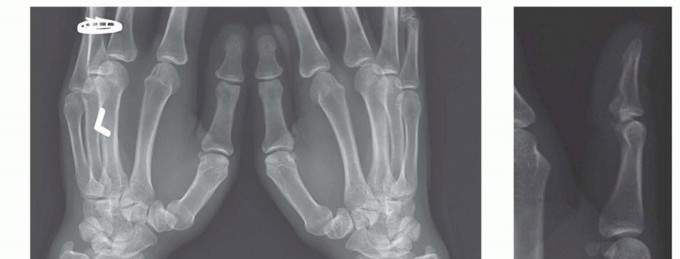

Proximal Interphalangeal and Metacarpophalangeal Joint Surface Replacement Arthroplasty